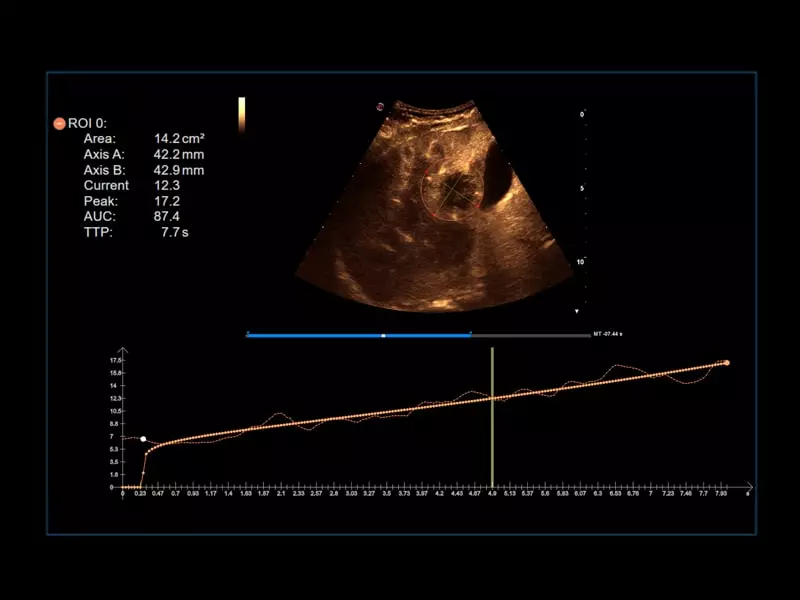

MyLab™9 Platform - QPack CnTI™ perfusion analysis post RF ablation

MyLab™9 Platform - QPack CnTI™ perfusion analysis post RF ablation